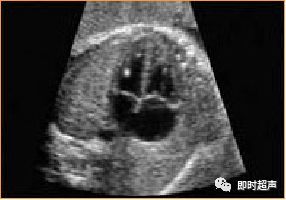

十一、室间隔缺损(VSD)

超声特点:常见的一种CHD,占其中20-25%可与其他心内畸形并存。

超声诊断VSD意义评估:①单纯VSD一般临床预后好,建议行染色体核型分析合并染色体异常的发生率18%。②VSD与其他心内或心外畸形并存预后多不良,可选择终妊妊娠。③不要因单纯VSD改变分娩方式和时间,出生后小缺损可自然闭合,大则及早手术修补 。